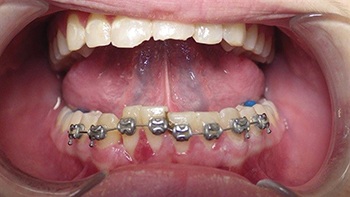

Figs. 3-4: Initial Appointment

Figs. 5-6: One-week follow-up showing early alignment after placement of brackets and light NiTi wire.